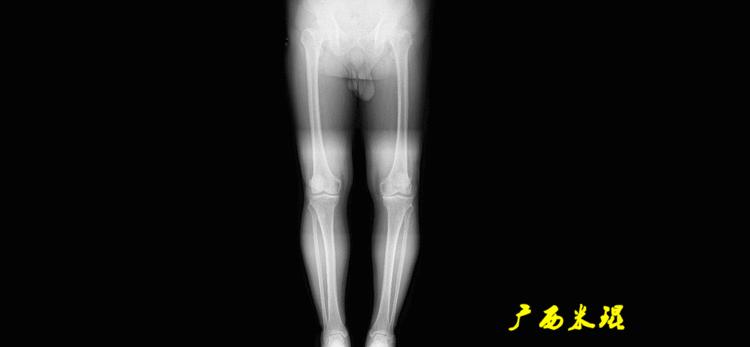

最常见的下肢畸形发生于冠状面,即膝内外翻畸形,冠状面的对线异常通过应用“对线异常检验”进行分析,机械轴的偏移(MAD)表现为对线异常。

膝内翻是指下肢力线通过膝关节中心点内侧,距中点2mm以上,偏内超过15mm为显著膝内翻。膝外翻是指下肢力线通过膝关节中心点外侧,距中点2mm以上,偏外超过10mm为显著膝外翻。

解剖股骨远端外侧角(aLDFA):股骨干下段轴线(解剖轴)与股骨内外侧髁远端切线(关节线)在膝关节外侧所形成的夹角,正常为81°±2°。大多数膝外翻患者的畸形发生于股骨下端,表现为股骨远端外侧角小于正常值。

膝外翻,下肢力线外移,Q角增大,髌骨外移趋势更加明显。